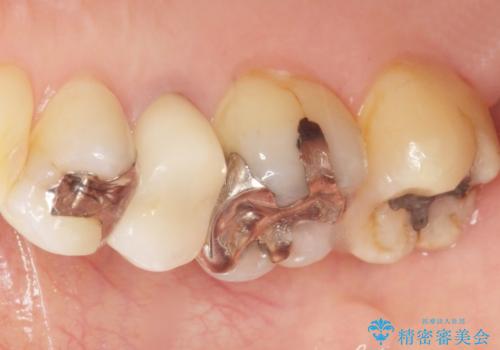

自然な見た目と咬み心地にご満足頂けました。

オフィスホワイトニングを行い、白くなった天然歯に合わせたシェード(お色味)でクラウンを作製しました。

モチベーションが上がり、他の銀歯もセラミックで治していきたいとご希望され、現在治療中です。

クラウンの種類:オールセラミッククラウン スタンダード